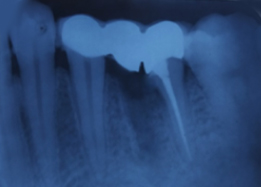

Pre-OP IOPAR